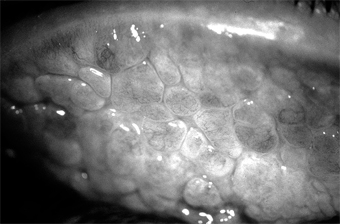

The patient usually complains of extreme itching and a ropy discharge. There is often a family history of allergy (hay fever, eczema, etc) and sometimes in the young patient as well. The conjunctiva has a milky appearance, and there are many fine papillae in the lower tarsal conjunctiva. The upper palpebral conjunctiva often has giant papillae that give a cobblestone appearance (Figure 5-11). Each giant papilla is polygonal, has a flat top, and contains tufts of capillaries.

Figure 5-11

Figure 5-11: Vernal keratoconjunctivitis. "Cobblestone" papillae on superior tarsal conjunctiva.